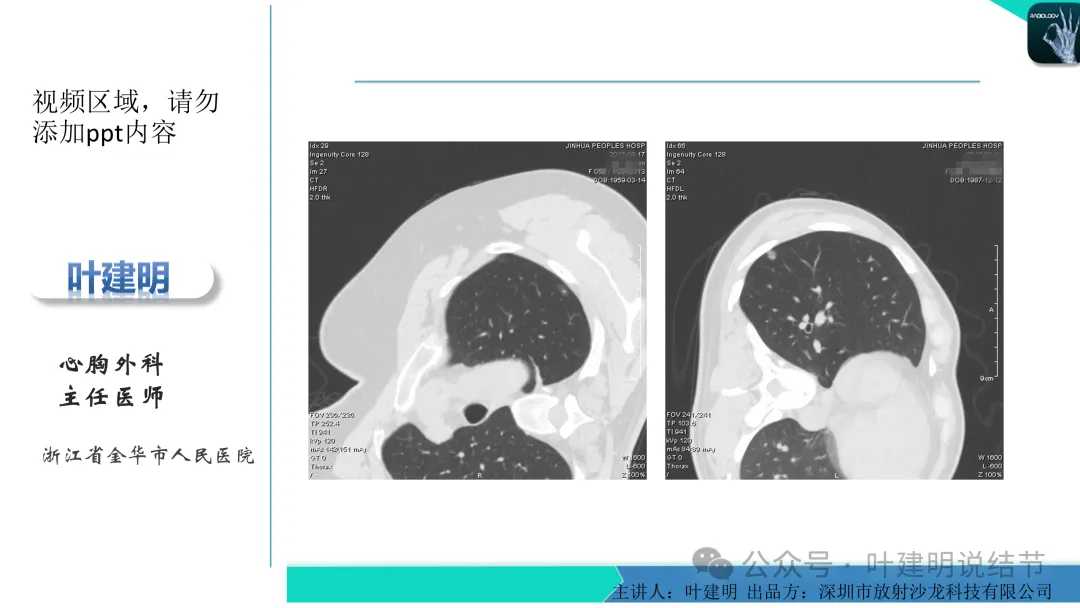

当地说考虑微浸润性腺癌的左下主病灶影像连续层面展示:

病灶出现,显模糊。

上图层面轮廓较清,但密度很淡,似见血管走行,但靠左前方的似条状磨玻璃密度与血管连着的到底是血管分支还是结节的一部分,其实并不确切。如果其实是血管分支,那病灶与它之间就不是空泡。

病灶在此层整体边缘显糊,灶内有空泡似的,瘤肺边界欠清。

边缘不平,还是灶内多发小空泡?邻近血管与之紧贴,但血管无异常走行。病灶密度很低,显糊。

中间所谓空泡更像是细支气管扩张,内壁非常光滑且圆形。

病灶边缘区淡而模糊。

上图是当地的影像报告,印象是两肺多发小结节,随诊。这很非常正常,也是合理的。结果骚操作来了!请该省级胸科医院教授会诊!下面是会诊时的意见:

某省胸科医院医生会诊后给出的意见是:左下肺后基底段(结节)达Lung-rads4B类,微浸润性腺癌可能,建议手术干预。签名的是B医生,后面给出了周一A主任肺结节门诊,周四B主任门诊。大概是团队成员,A医生是著名大咖,B医生是团队骨干成员!

这个病灶会是微浸润性腺癌吗?当然没有病理诊断,我也不能说百分之百必不会,但这样的病灶已经风险大到必得尽快手术切除干预了吗?显然还早着呢:1、影像不是典型的结节状;2、边缘与轮廓模糊不清;3、灶内似有细支气管扩张(更容易是细支气管扩张伴少许周围炎或肺泡上皮增生);4、血管邻近走但无牵拉影响;5、没有实性成分,没有锐利毛刺,没有胸膜牵拉,没有血管进入,没有任何倾向风险性高的影像特点。我一直强调:肺结节是否要干预处理,不要纠结于最后病理是什么,而要看风险高低;而风险高低的最重要术前判断依据一是随访有无进展,二是有没有实性成分。只要没有肉眼可见的影像上的实性成分,风险就是低的!何况病理也是人看的,原位还是微浸润,不典型增生还是原位有时也在一念之间。